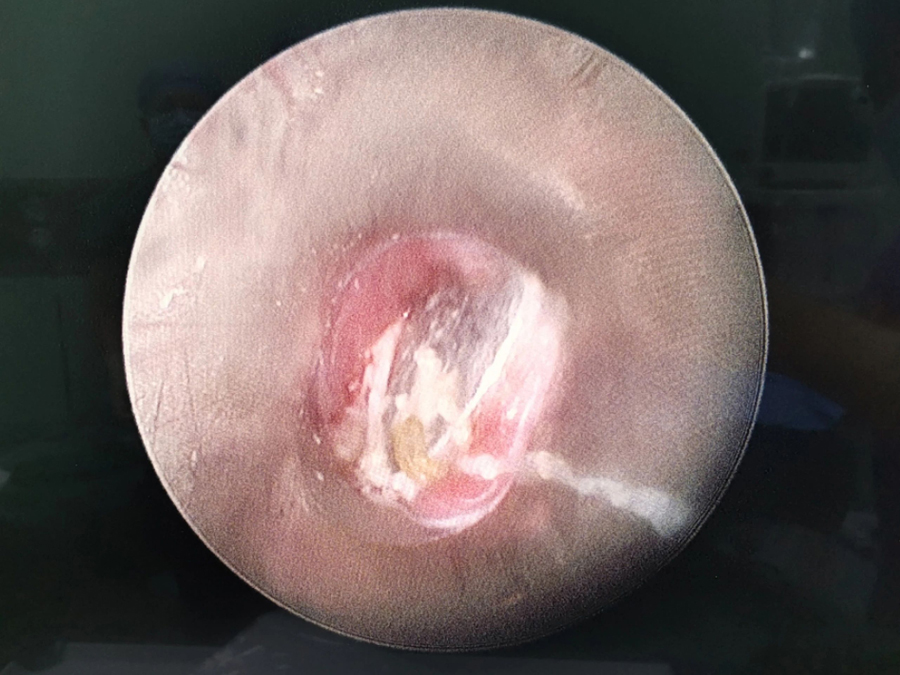

了解了患儿的情况后,国家儿童医学中心、首都医科大学附属北京儿童医院耳鼻喉头颈外科常驻专家、a片网站 副院长张薇仔细看了患儿的X光片,明确了异物的存在和准确位置。由于异物存留时间长,食道是否有肉芽增生、有无穿孔等情况都不明确,张薇副院长决定采用全麻下通过食道镜直视下行异物取除术。

手术非常顺利,当卡在小强食道入口下方的硬币被取出后,家长才知道,原来导致孩子受罪一个多月的竟是一枚硬币。由于硬币卡在食道内时间太长,被取出时颜色已经发黑。术后,小强不能像其他孩子一样迅速恢复呼吸,而是住进了ICU。原来是由于异物坎顿,食道入口关闭不全,小强进食时总会呛咳,导致反复吸入性肺炎,肺功能明显受损,肺内通气量不足、反复发热,全身身体机能下降,所以不能及时苏醒。不过,经过医务人员进一步治疗后,小强现已康复出院。

小花的情况比小强好一些,硬币被取出后,顺利回到病房,经过两天住院观察和治疗就出院了。